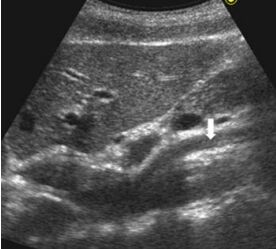

61.肝臟超音波橫向掃描時,在外側節段(lateral segment, L)與尾葉(caudate lobe, C)之間有 一高回音裂隙(fissure, F),如下圖箭號處。此高回音裂隙與下列何者最有關係? (A)靜脈韌帶(ligamentum venosum) (B)動脈韌帶(ligamentum arteriosum) (C)圓韌帶(ligamentum teres) (D)鎌狀韌帶(falciform ligament)